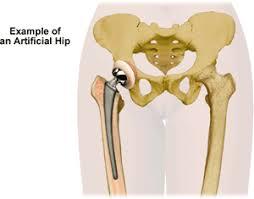

Understanding Artificial Hip Joints

Artificial hip joints are prosthetic implants used to replace damaged or diseased hip joints. The artificial joint typically consists of three main components:

- The femoral component — replaces the top of the femur.

- The acetabular component — replaces the hip socket.

- The bearing surface — allows smooth joint movement.

Materials used include metals (titanium, cobalt-chrome alloys), ceramics, and medical-grade polyethylene.